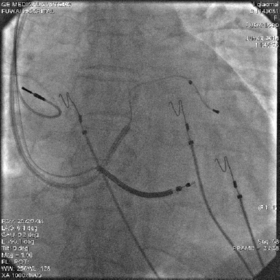

最终影像

AP

LAO

RAO